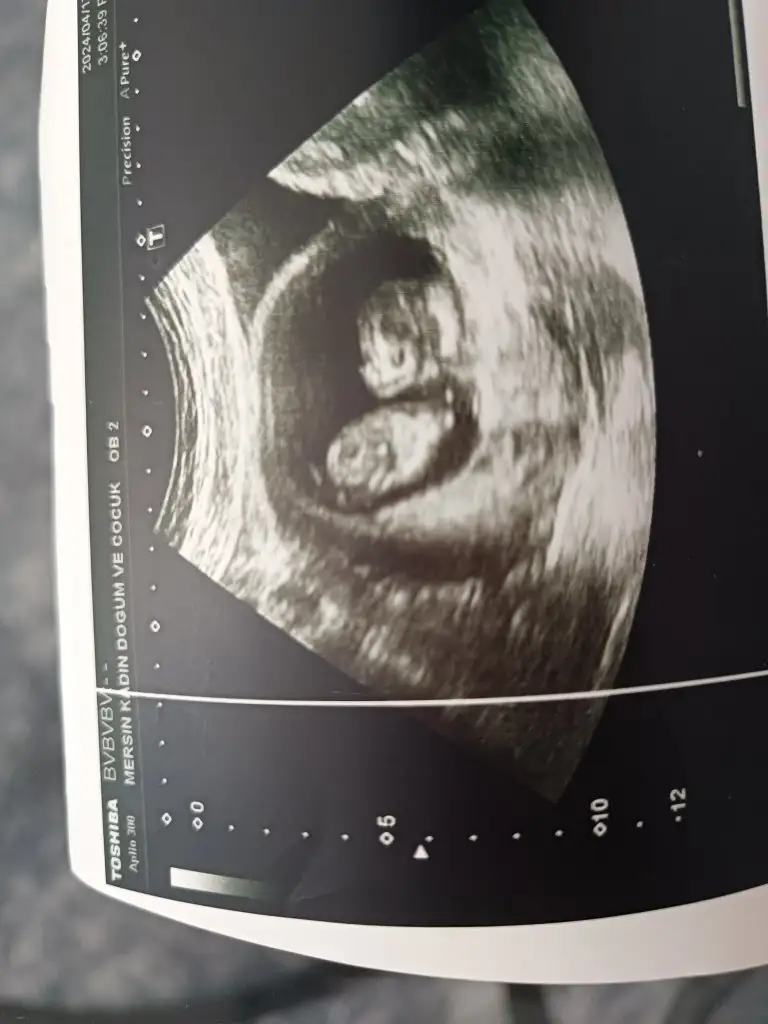

Bana da tahmin yapabilir misiniz

Eklentiler

• IMG_3528.webp

IMG_3528.webp

17,8 KB · Görüntüleme: 58

• IMG_3603.webp

IMG_3603.webp

31,4 KB · Görüntüleme: 46

• IMG_3545.webp

IMG_3545.webp

21,4 KB · Görüntüleme: 48